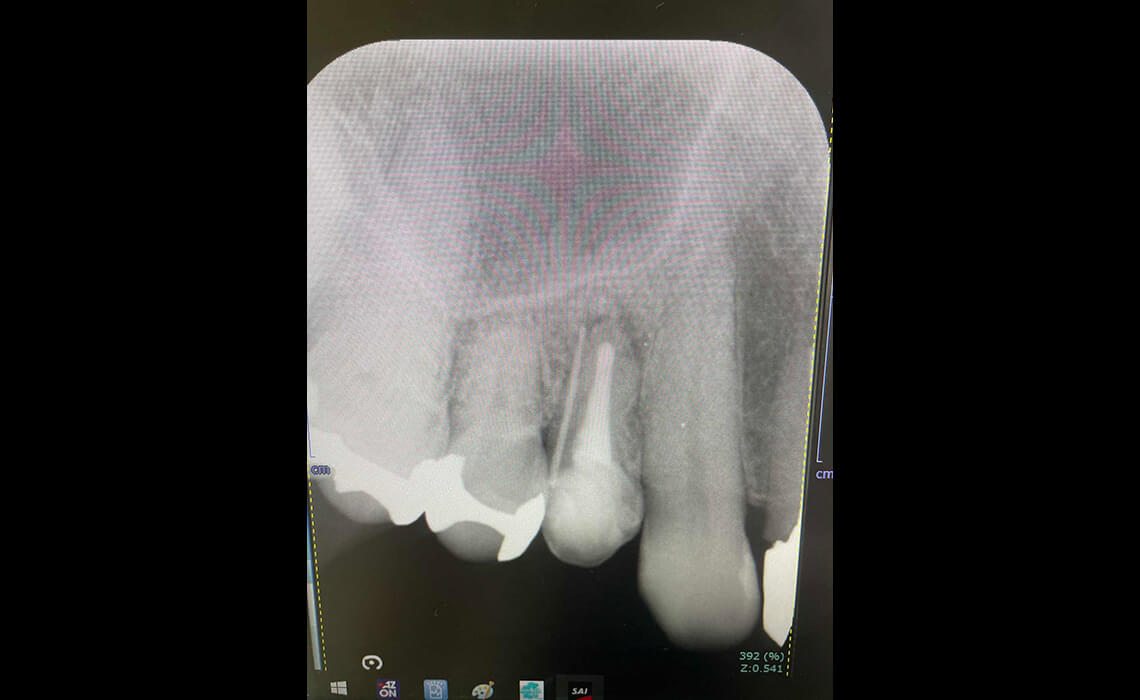

まずはカウンセリングと診査を行います。デジタルレントゲンやCTで歯の内部や根管の形を正確に把握し、治療計画を立てます。

当院ではマイクロスコープを用いて、肉眼では見えにくい複雑な根管内部まで拡大視野で確認します。感染源となる神経や歯質を丁寧に除去し、治療の精度を高めます。

治療後も定期的なレントゲン検査やメンテナンスを行い、歯の状態を確認します。長期的にご自身の歯を守るために継続的な管理が大切です。